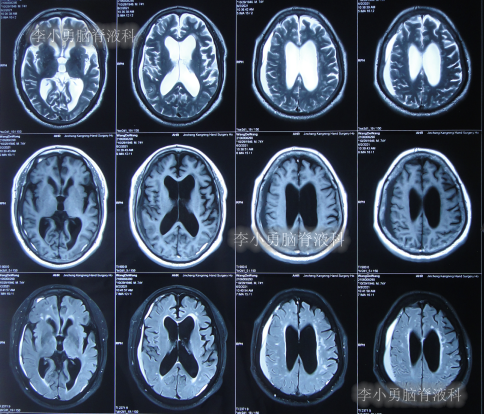

出院后再次转住入当地的第1家医院进行康复治疗,在该院康复治疗半年多的时间,不但没有持续好转,反而再次腰疼,走路不稳,且还出现了尿失禁的持续加重症状;治疗期间曾6次查头部影像(图-13、图-14、图-15、图-16、图-17)均示脑积水不断加重的趋势。

图-13:2021年5月22日头部核磁

图-14:2021年6月2日头部核磁

图-15:2021年7月24日头部核磁

图-16:2021年8月28日头部核磁

图-17:2021年9月28日头部CT